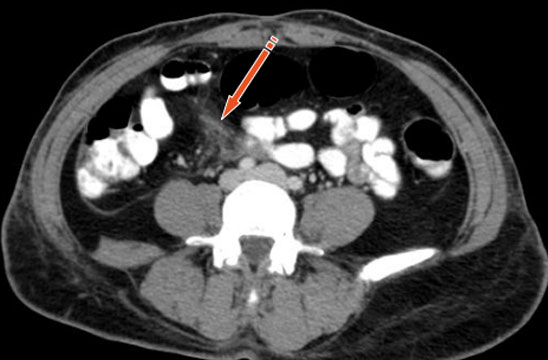

Se presenta un caso de lesión mesentérica en el contexto del "síndrome de cinturón de seguridad". en una acompañante delantera tras un choque frontal a alta velocidad, tratado conservadoramente. Se revisa la utilidad de la TC para el diagnóstico precoz de esta lesión, que debe sospecharse cuando está presente el signo del cinturón de seguridad en la pared tóracoabdominal.